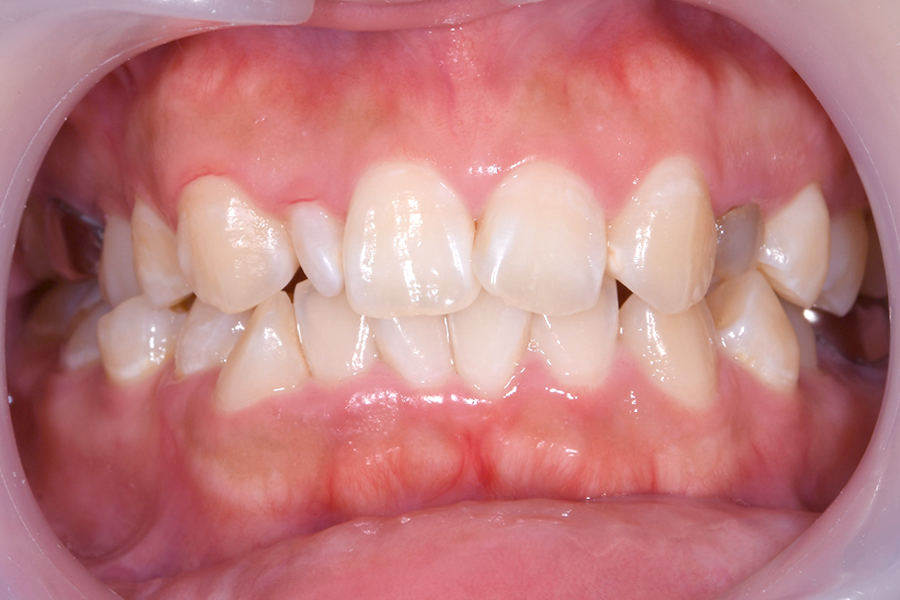

case3

術前

術後

| 主訴 | 前歯が欠けた、少ししみる |

|---|---|

| 治療内容 | 神経が露出ていたため歯髄温存療法を行い、両隣の歯の形や大きさを考えダイレクトべニアで修復しました。 |

| 治療費用 | 歯髄温存療法とダイレクトべニア 138,600円(税込) |

| 治療期間 | 1日 |

| 治療のリスク | 治療によっては歯の体積を削る量が多い場合があります。 |

| 治療の副作用 | 治療後、軽い出血や痛みを伴う可能性があります。 稀にセラミックが欠ける場合があります。 |